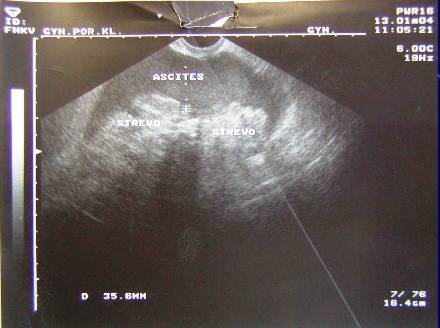

3.Duplicita (pac.M.B.-tu markery, laparotomia, radikální operace pro Ca ovarii, peroperační biopsie)

Duplicita (pac.M.B.-tu markery, laparotomia, radikální operace pro Ca ovarii, peroperační biopsie)

Duplicita(pac.M.B.-tu markery, laparotomia, radikální operace pro Ca ovarii, peroperační biopsie)

Duplicita (pac.M.B -laparotomia, radikální operace pro Ca ovarii, peroperační biopsie)